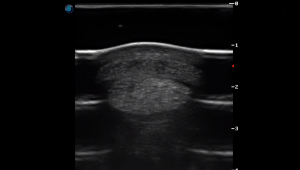

SIMON Ultrasound Database

This ultrasound database is a free resource for students and doctors!

Our collection includes videos of dogs, cats, horses, cows, humans, and many other species!